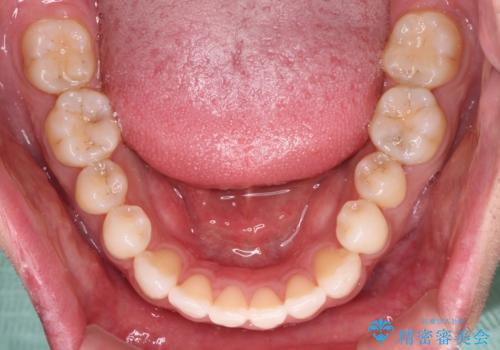

- 上下前歯の叢生を気にして来院された患者様です。

費用を抑え、期間もあまりかけずに治療をしたいとのことで、インビザライン・ライトを用いて矯正治療を行うこととしました。